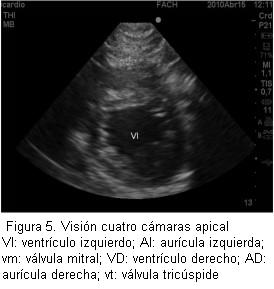

Los resultados de este taller demuestran claramente que se cumplió con el objetivo planteado al inicio: enseñar los principios básicos de ecografía transtorácica y ecografía para punción vascular. Esto se evidenció en la clara mejoría de los resultados de la prueba aplicada antes y después del taller (figura 3). Así con la realización de una introducción teórica y estaciones prácticas (figuras 4 y 5) se logra un significativo avance en la comprensión de la ecografía por parte de los anestesiólogos.

Se ha planteado que el examen ecocardiográfico transtorácico que realiza un anestesiólogo es completamente diferente al examen que realiza el cardiólogo y, por supuesto, no pretende de manera alguna reemplazarlo. Esto se explica porque el anestesiólogo busca resolver preguntas concretas con respecto a lo que ocurre con el corazón en el paciente en su perioperatorio: el estado de la volemia, la contractilidad y tamaño de las cavidades cardíacas. Existen varias publicaciones que avalan la utilidad de la ecocardiografía para los anestesiólogos. Uno de los primeros estudios fue hecho por el grupo de Sloth (6), que evaluaron a pacientes hemodinámicamente inestables en su postoperatorio y obtuvo imágenes satisfactorias por encima del 80% de los casos e imágenes que fueron útiles como guía y manejo de estos pacientes. Durante el preoperatorio se ha planteado la gran utilidad que puede tener la ecocardiografía para evaluar pacientes con presencia de soplos en el examen físico, con capacidad funcional no evaluable y aquellos pacientes con severa alteración de sus capacidades mentales (enfermedad de Alzheimer, deterioro senil) (7). En el intraoperatorio realmente puede ser útil para la monitorización del estado hemodinámico de manera no invasiva (8,9), que permite realizar nuevos diagnósticos, iniciar nuevas terapias y reemplazar otras formas de monitorización, como línea arterial o catéter venoso central. Otra indicación que puede resultar muy interesante es la alta utilidad que puede tener la ecografía durante las maniobras de resucitación cardiopulmonar, ya que en períodos muy breves de detención de las maniobras de masaje cardíaco externo, es posible visualizar a través de la ventana subcostal qué sucede realmente con el miocardio, y es así que se ha demostrado que no siempre el diagnóstico de actividad eléctrica sin pulso corresponde a esta entidad (10).